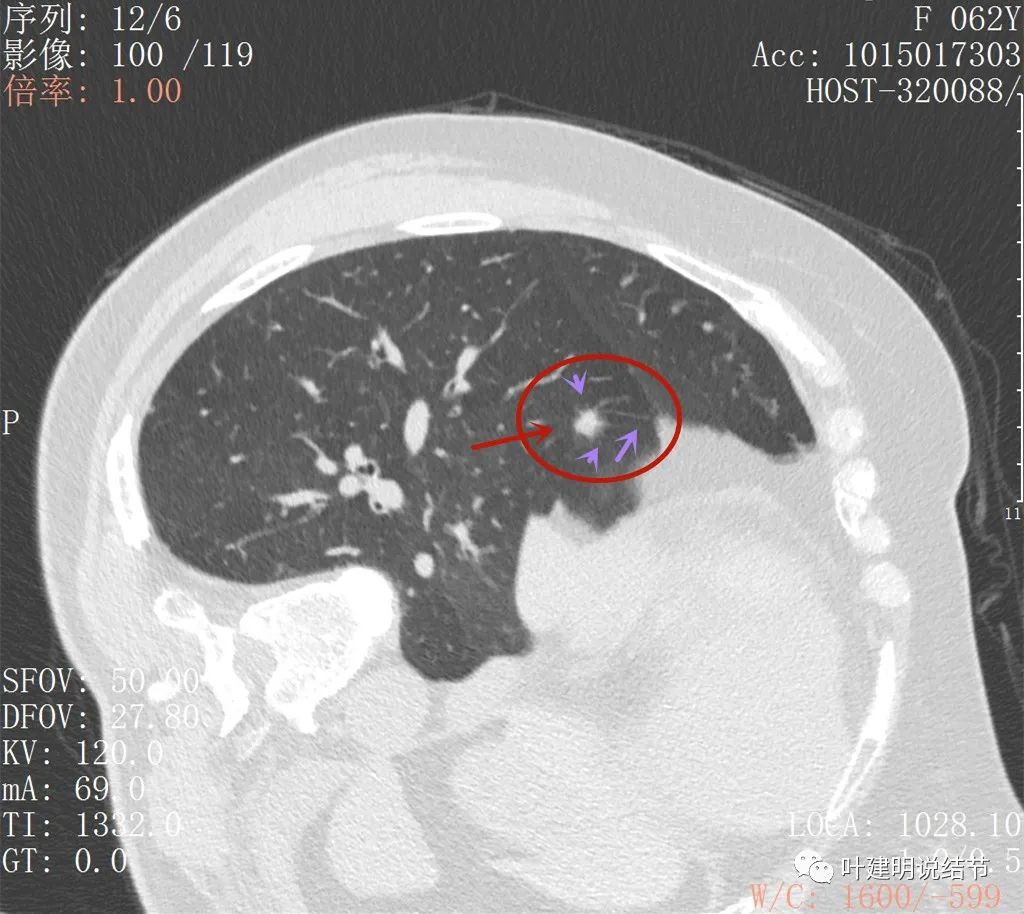

前次手术时右下结节偏实性,不太致密,边缘显模糊,还不能认定为恶性,但需随访观察对比

到了一年后,这结节没有吸收好转,反而边上较前清楚了一点起来,仍像磨玻璃过渡到实性的阶段(偏实性,但又不是很密实)

到了今年1月份时,结节还在,瘤肺边界似较前清楚了点

这是最近一次平扫的片子,此结节感觉有膨胀感,边界较清,位于肺底,贴膈面。我们从数次复查的对比,看来该结节是缓慢进展的,不吸收也不钙化,也不是纤维增生或条索状瘢痕的样子。在门诊我仔细对比了这些不同时间的片子后,认为右下这结节也极可能是恶性的,该干预。所以我们进一步查了靶扫描: